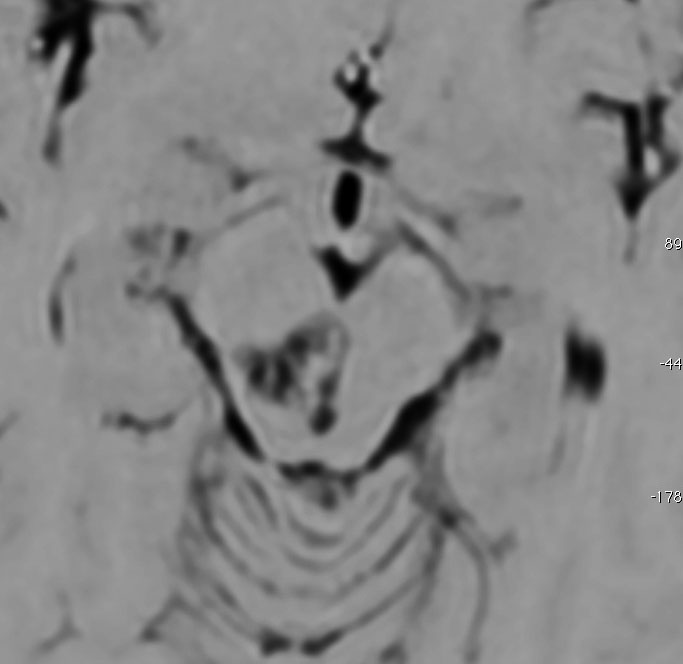

手術後のMRI

手術後にガドリニウム増強MRIで脳脊髄播種がないかどうかの確認をしました。腫瘍は全摘出できていて,複視や視野障害などもなく無症状です。